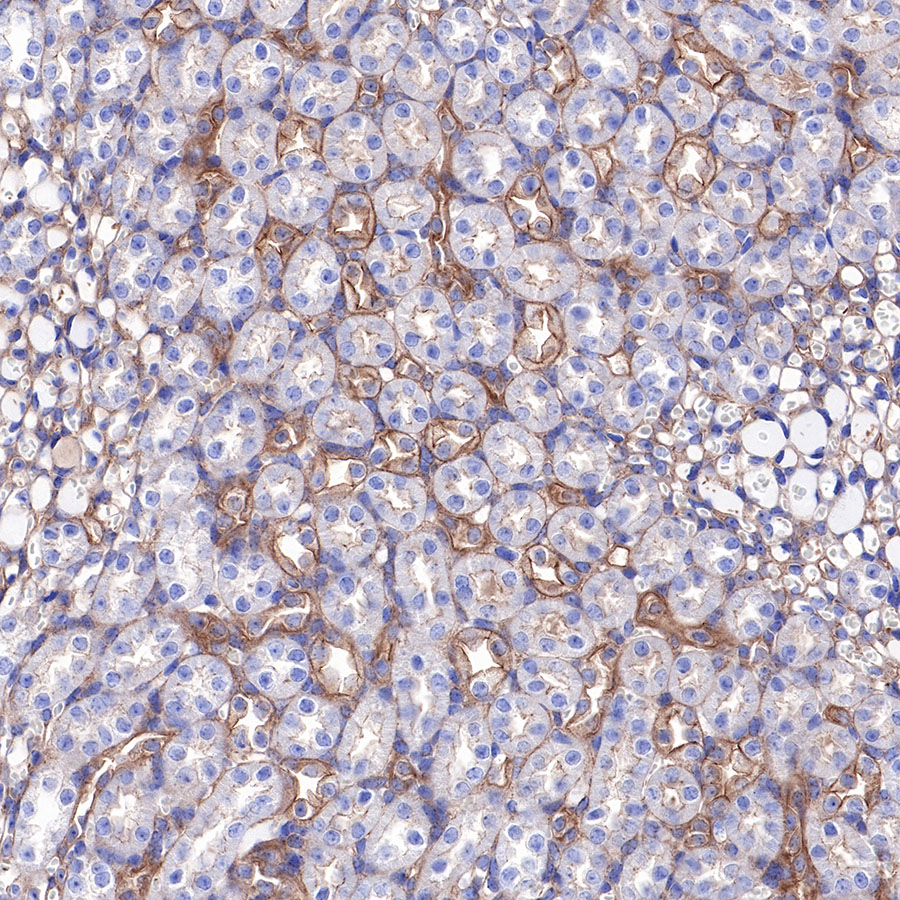

IHC shows positive staining in paraffin-embedded human pancreatic cancer. Anti-α-Actinin-1 antibody was used at 1/2000 dilution, followed by a HRP Polymer for Mouse & Rabbit IgG (ready to use). Counterstained with hematoxylin. Heat mediated antigen retrieval with Tris/EDTA buffer pH9.0 was performed before commencing with IHC staining protocol.

IHC shows positive staining in paraffin-embedded human breast cancer. Anti-α-Actinin-1 antibody was used at 1/2000 dilution, followed by a HRP Polymer for Mouse & Rabbit IgG (ready to use). Counterstained with hematoxylin. Heat mediated antigen retrieval with Tris/EDTA buffer pH9.0 was performed before commencing with IHC staining protocol.